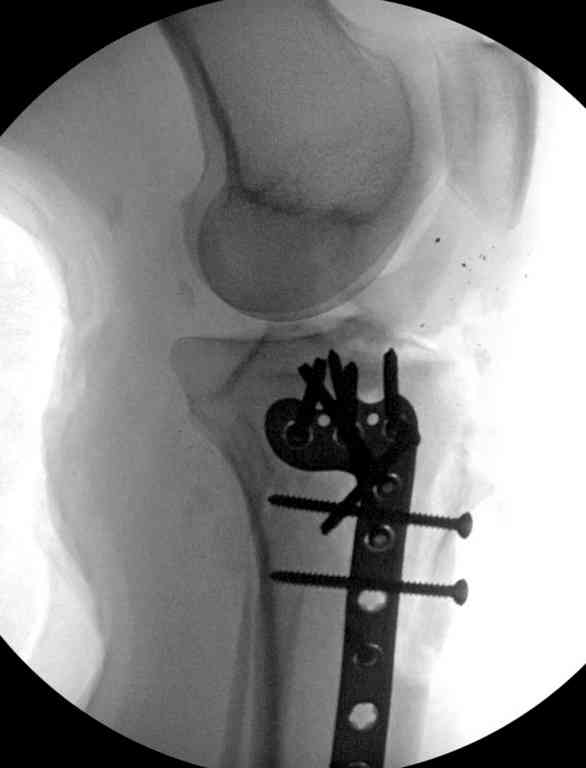

Здесь применение материала Plexur http://www.plexur.com для пластики при дефектах кости у больной с огнестрельной раной латерального тибиал плато с повреждением малоберцового нерва. Несмотря на интактный медиальный мышелок, для профилактики от вальгуса установлен АВФ и сделана ангиограмма.

После нескольких обработок и вакуумирования, поэтапно сделана фиксация тибиального бугра шурупами. И окончательную фиксацию закончили латеральной пластиной для тибиал плато и установкой пластического материала.

Для закрытия мягкотканых дефектов привлечена другая служба.

План с протезированием чересчур агрессивный, больная слишком молодая. В данный момент для удержания конструкции необходимо установить наружный фиксатор между бедром и голенью. Обработку продолжать с применением антибиотиков и вакуумирования.